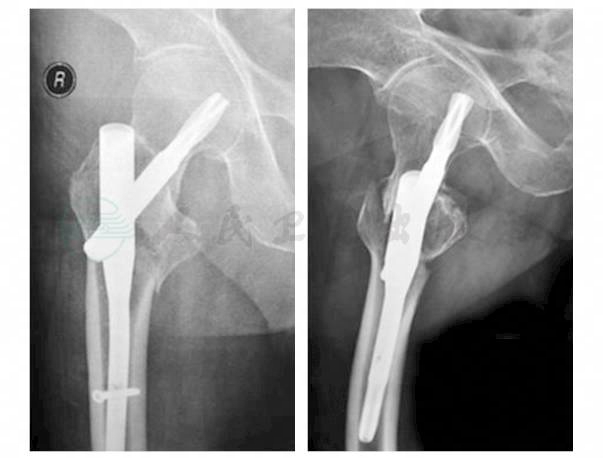

患者,男性,80岁。患者外出行走时摔倒,右髋部、右肩着地摔倒,导致右髋部、右肩疼痛4小时,于宣武医院急诊就诊,X线检查为右股骨转子间骨折、右肱骨近端骨折而收住院治疗(图1,图2)。查体:右髋、右肩肿胀,右下肢短缩外旋畸形。右髋、右肩关节活动受限,压痛阳性。既往高血压病史16年,药物可控制。脑血栓后遗留右侧下肢肌力下降,功能不良3年,借助步行器可外出行走。

图1 术前髋关节X线片

患者右股骨转子间骨折AO分型为A2型,小转子骨折,但其内侧皮质未见明显缺损。骨折复位固定后具有一定的稳定性,可考虑闭合复位、短髓内钉内固定的治疗方案。右肱骨近端为Neer二部分骨折,骨折复位后的稳定性可,二部分骨折复位固定后愈合率较高,也可考虑行骨折切开复位内固定术。

右股骨转子间骨折于麻醉成功后,患者置于牵引床上行闭合牵引复位,C形臂X线正侧位片见骨折复位良好。常规碘酒、酒精消毒后铺无菌单。触及右股骨大转子部并向近端延续2~4cm为切口起点,取长约3~4cm切口,依次切开皮肤、皮下组织、阔筋膜,钝性分离肌肉。触及大转子尖,置入导针,位置良好后置入髓内钉主钉。C形臂X线正侧位片观察主针深度及其前倾角,调整到良好位置及角度后,顺导钻打入股骨头颈内导针。再用C形臂X线机观察导针位置及其进针深度,均满意后测量其头颈内固定钉长。顺导针方向打入PFNA头颈固定钉,C形臂X线机探查见骨折复位良好,头颈内固定钉位置可。再于外侧导向装置,由套筒导引钻孔后打入远端锁定。冲洗伤口,留置引流管1枚,逐层关闭伤口。无菌敷料包扎,手术顺利,麻醉满意,术中出血约30ml。术毕活动髋关节,见关节活动良好。术后24小时后移除引流管,并将床头抬高30°~40°以减少患者进食或咳嗽时的不适。术后第2天行X线检查示骨折复位满意,正位片见内置物位置良好,侧位片见头颈内固定物偏前(图4)。

图4 术后髋关节X线片